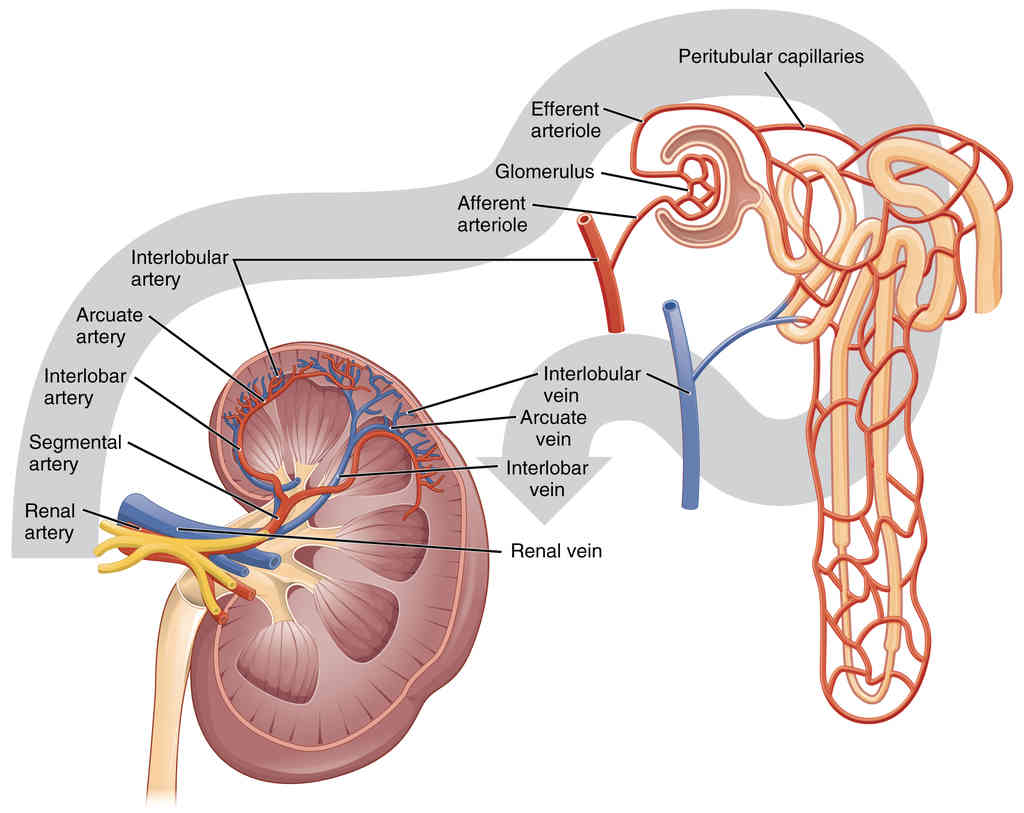

This page is under construction. For now, it is just a resource of the images found in the OpenStax Anatomy and Physiology Handbook. It wil slowly change into a revision tool. Each slide has a number. Use this to refer to the slide. When completed, it will have an unlabelled section, with labelled slides in parallel. On the unlabelled slides, write your answer and use the labelled slide to assess yourself. Keep track by also noting the number on each slide. Improvement at each attempt is important, more so than full marks on a first attempt.